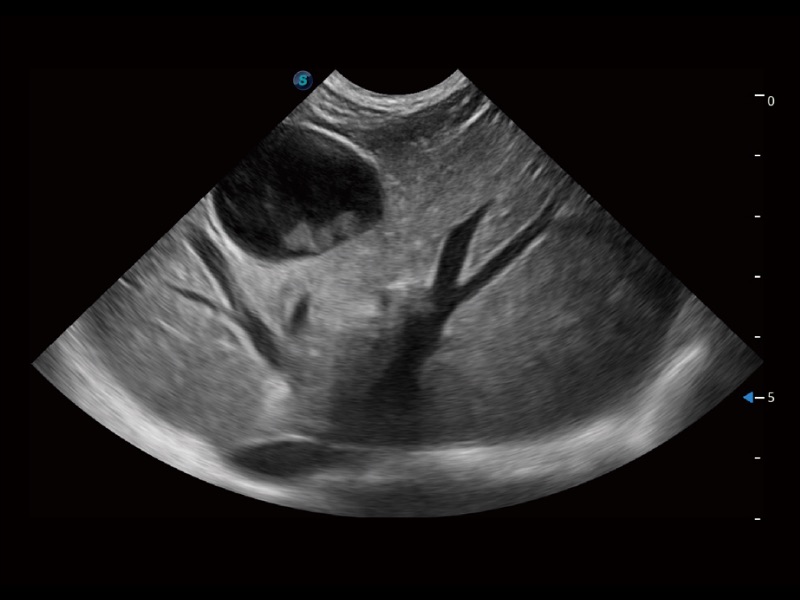

一键自动识别膀胱壁及自动测量膀胱容积,不受膀胱形状和大小的限制,帮助医生快速精准获得测量的数据。

ProPet 70专为动物医生设计,对不同的动物体型和生理结构作出了针对性的优化。通过动物影像专用软件,可满足个性化的应用需求,帮助动物医生获得更精确的诊断数据。

为精细结构及组织边缘提供高清晰度的图像和更大的成像视野。帮助减轻医生的用眼疲劳,快速精准获得测量的数据。